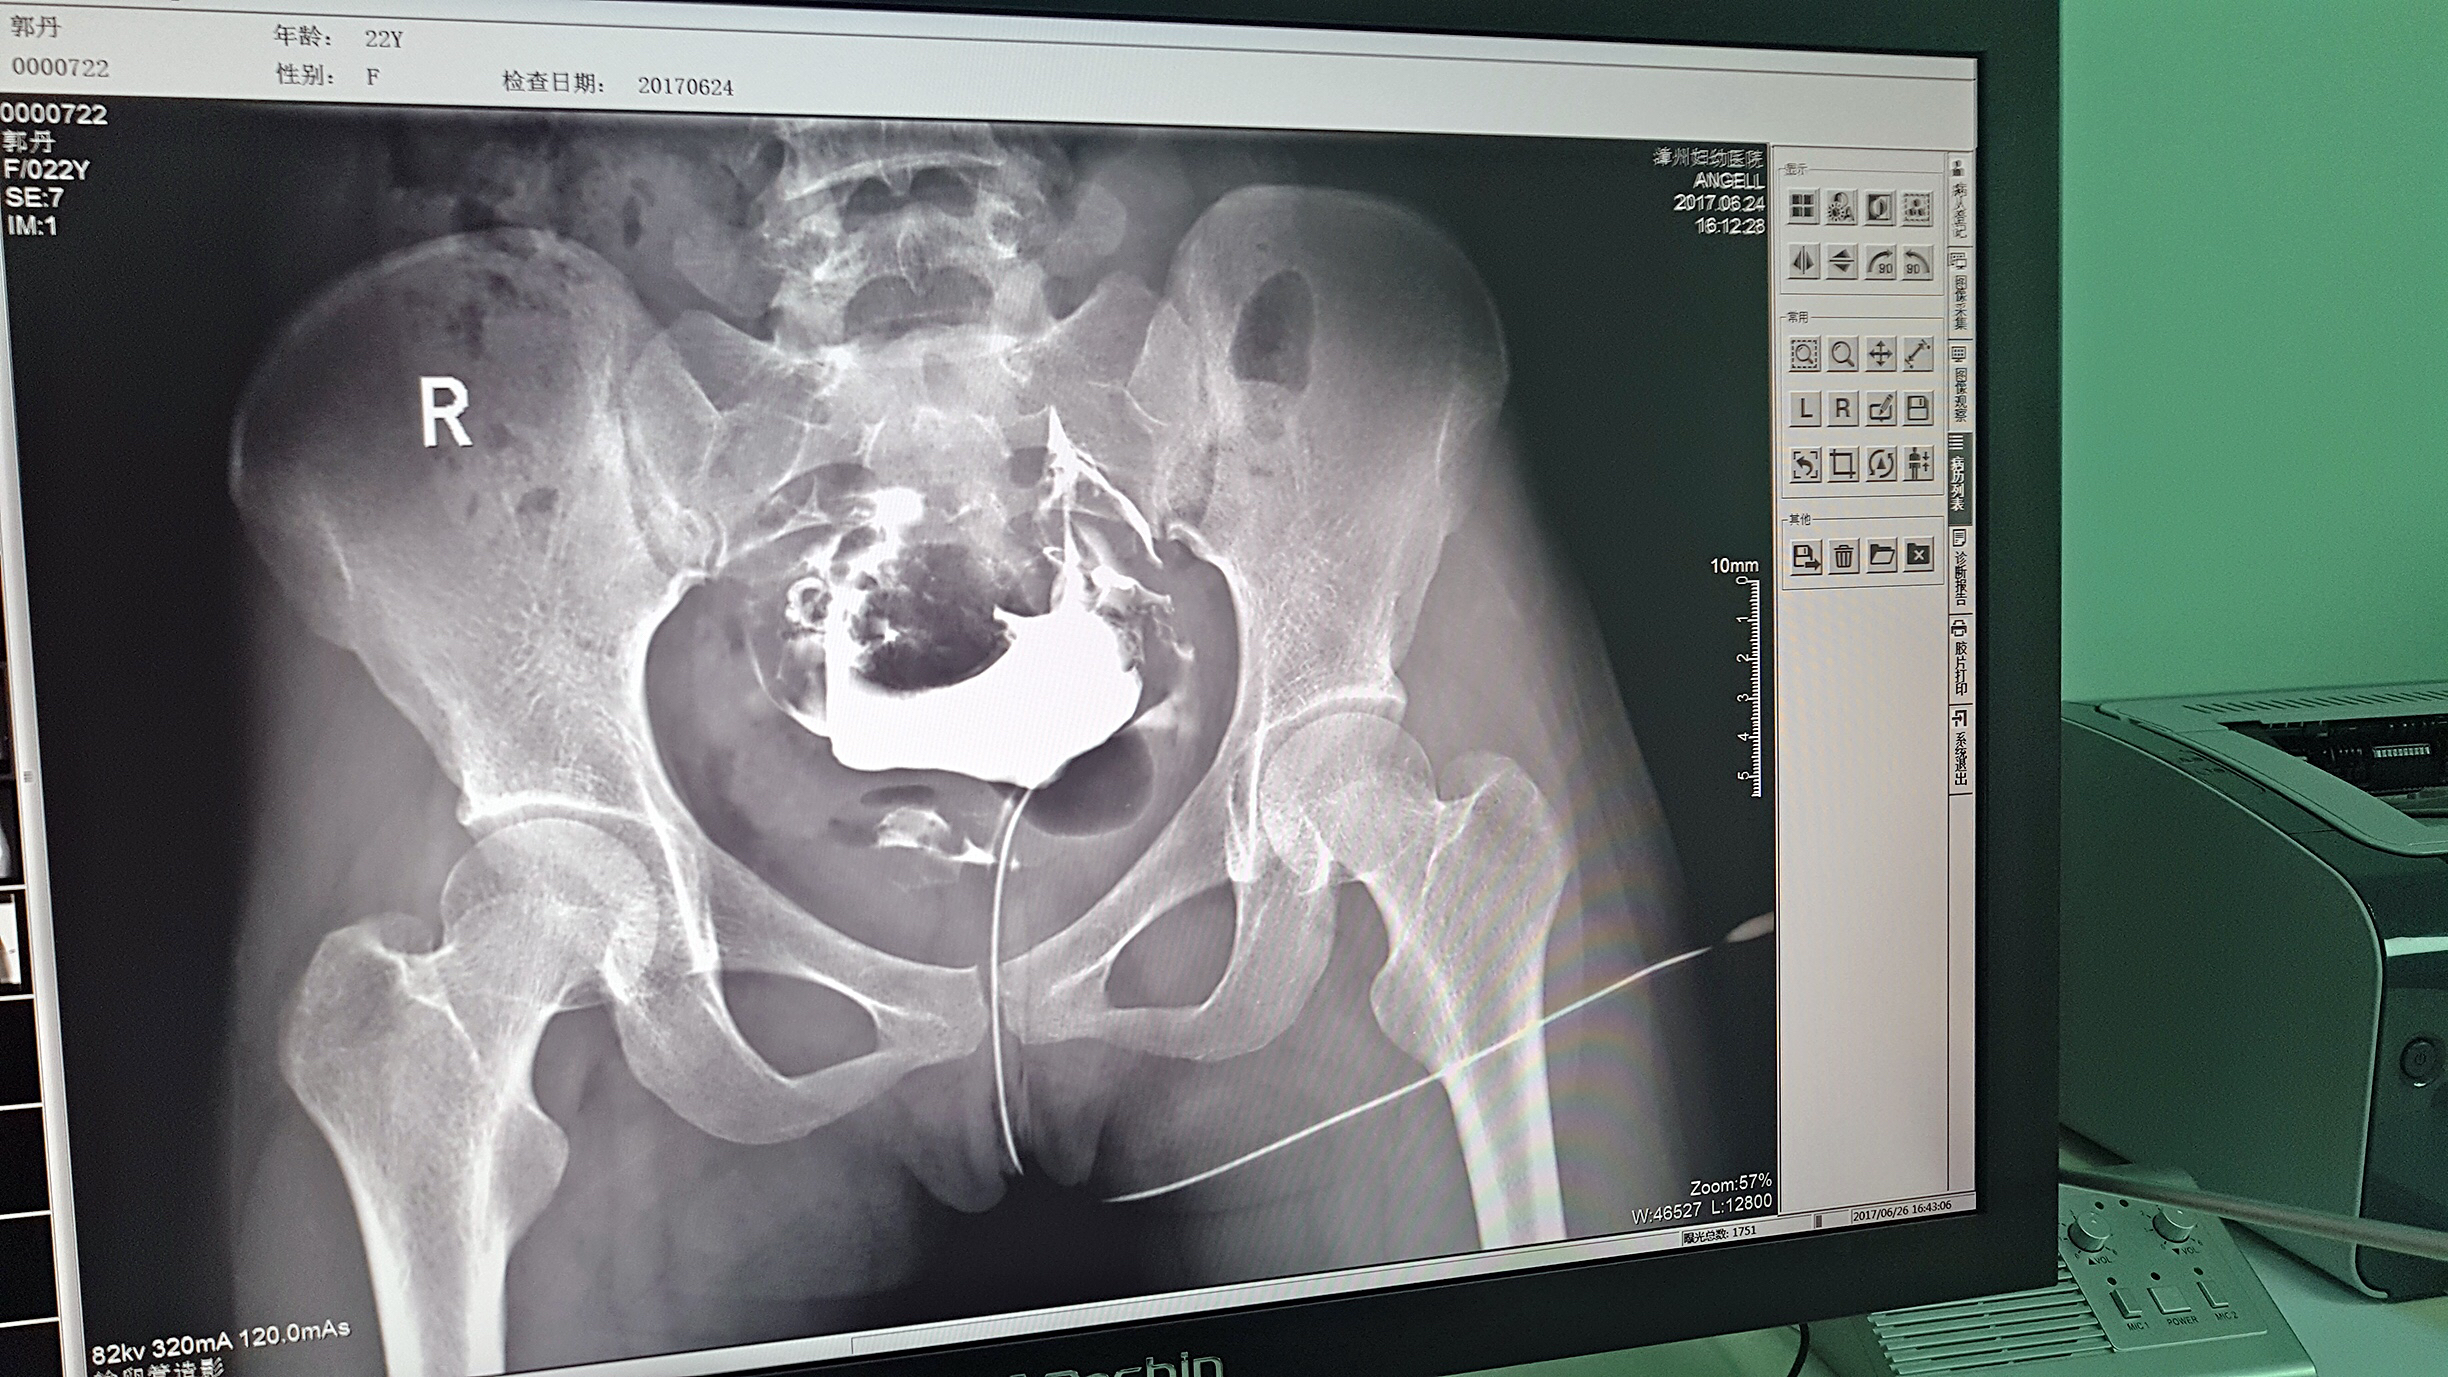

但是这家医院一直面临一个问题,妇科中输卵管检查无法完成。因为其使用的是静态DR,无法做输卵管造影检查,患者不得不前往其他医院继续检查,使得医院留不住患者,造成一笔损失。久而久之,患者可能为了图方便,直接去了其他医院治疗,这对医院经营的影响是巨大的。

2016年,漳州妇幼医院几经对比、筛选,最终选择了广东会科技的动态DR产品。它选择广东会科技动态DR产品的原因很简单,动态DR不仅具备普通DR的功能,还能做输卵管造影,成像质量高以及设备性价比高。

目前设备除了用于常规拍片之外,主要用于输卵管造影检查,平均每个月有超过20个患者在漳州妇幼医院做输卵管造影检查。在此之前,漳州市只有市医院、175解放军区医院等大三甲医院才能做输卵管造影检查,这不仅让三甲医院人满为患,而且下级医院却因为不能做某项检查而造成资源浪费。因为有了设备,漳州妇幼医院可以满足患者的一些特殊检查需求,已经有很多患者慕名而来。

漳州妇幼医院放射科的陈主任日常跟这台设备打交道是最多的,他最有发言权。在广东会科技的回访中,陈主任说:这台设备具备先进的诊断功能,操作方便,能够拍摄出清晰的影片,进而对患者病情能够实现精准诊断。同时在医院对患者诊断能力方面有较大提升,留住了大量患者,为患者提供了更好的医疗服务。